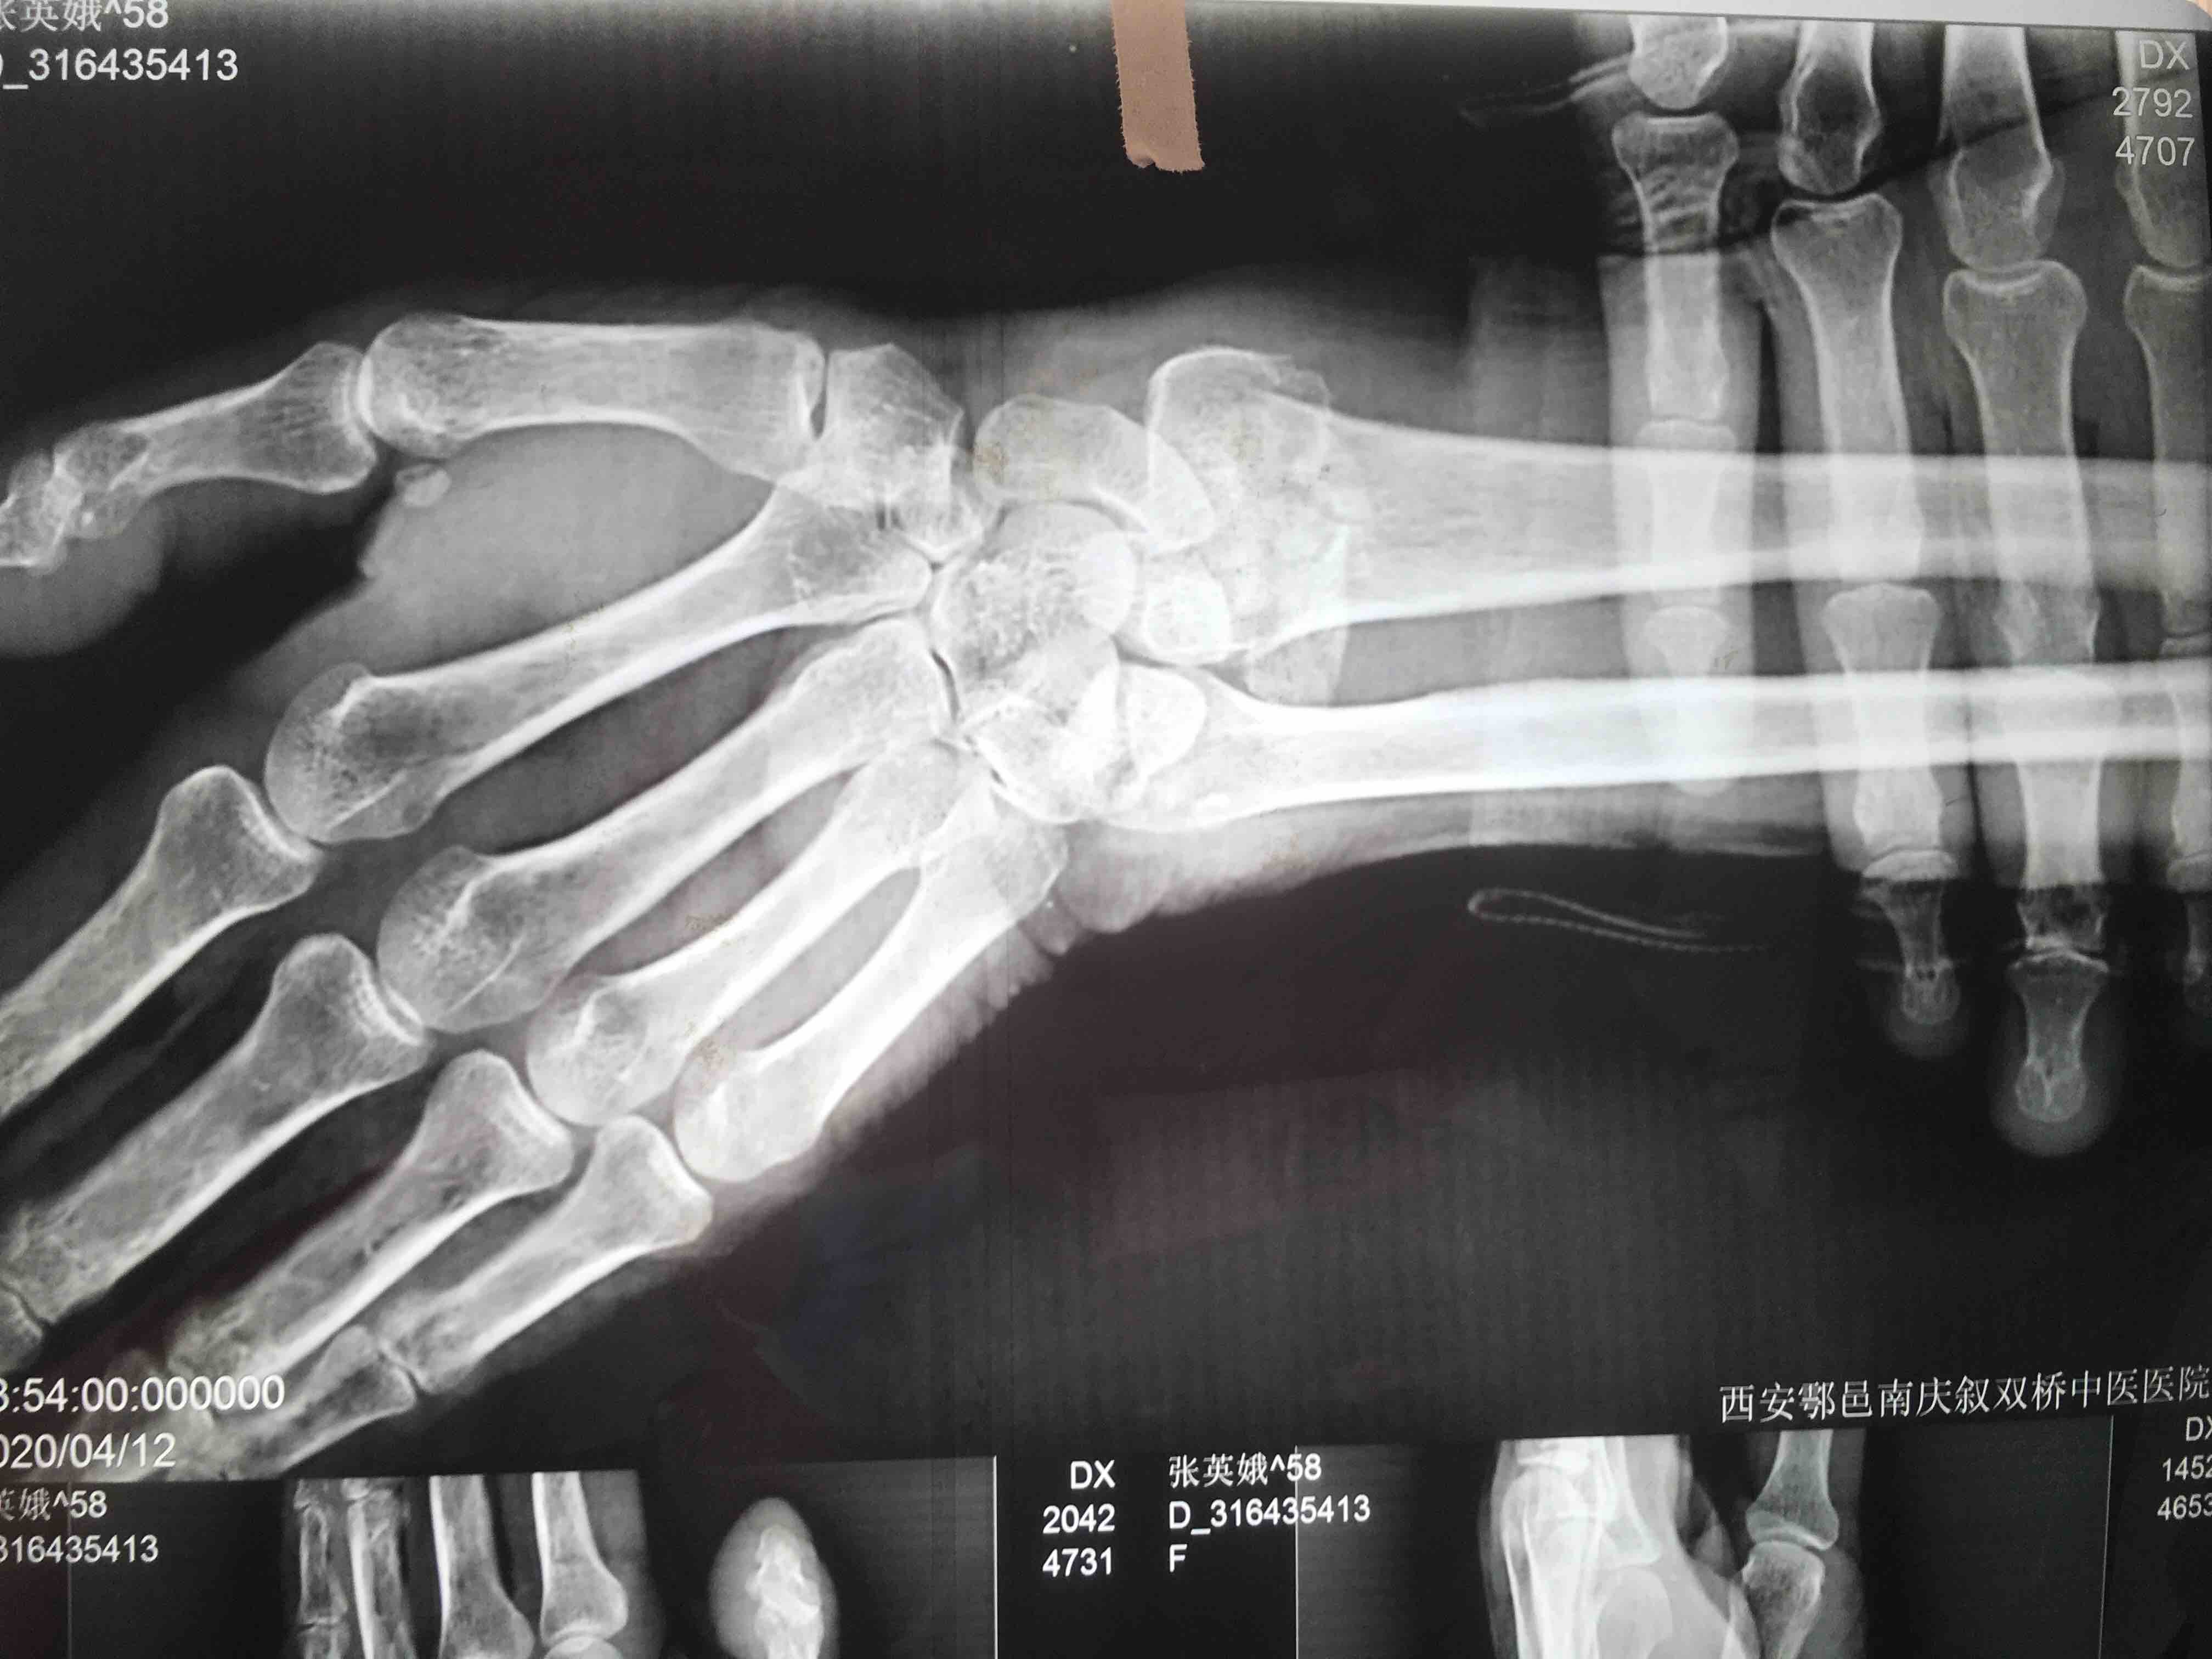

打开应用老年患者colles骨折(切复内固定术)

患者:女/七十四岁

摔伤后左肿痛,活动受限1小时入院。

左腕部肿胀明显,畸形,局部压痛及纵向叩痛阳性,活动受限,末梢血运感觉正常。

诊断 治疗

在臂丛麻醉下行切复内固定术,术后抗炎对症处理。